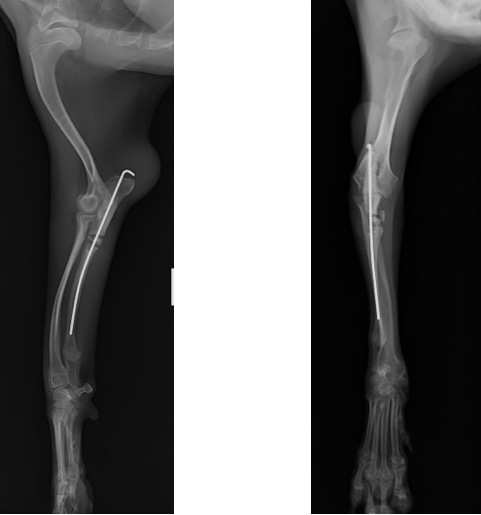

術後のLateral像とAP像 (前例と同じく髄内ピンとしてK-wireを刺入したのちに切り取った骨片を破砕し、骨切部分へ再移植しました。)

術後1ヵ月 (移植した骨が少しずつ癒合し始めてきましたが、K-wireの先端が軟部組織を刺激してしまっているためか、肘頭の腫脹が認められました。)

術後2ヵ月 (K-wireの先端が軟部組織を刺激し、患肢の着地を阻害していると考えられたため、抜ピンを実施しました。)

術後3ヵ月 (移植骨の癒合良好で、K-wireの刺入孔も不明瞭化してきました。)

術後6ヵ月 (骨切り線が完全に消失しました。)